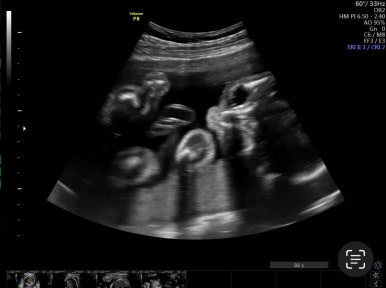

21주 1일

정밀초음파로 외형, 장기 등이 이상이 없는지 확인하는 시기이다.

머리부터 발끝까지 꼼꼼하게 검사를 하게 된다!

손발 등 너무 정교하게 생겨서 너무 신기하다!